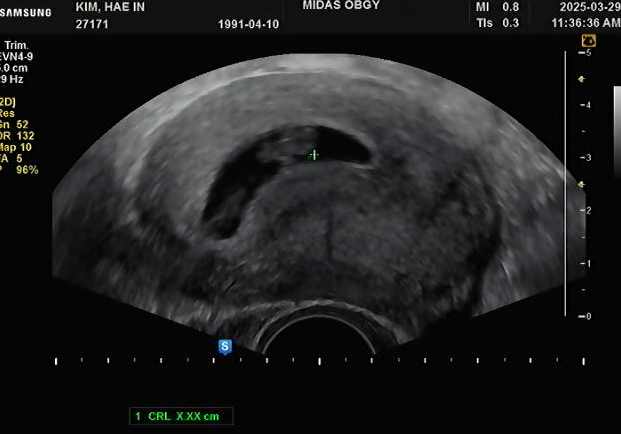

임신13주차 (25.05.10) 저번 하혈 이슈로 한주 미뤄진 기형아 검사 초산치고는 어린나이가 아니라 걱정이 ...

임신 7주차 증상 / 보건소 산전검사 결과 / 입덧+먹덧

임신 7주차 (25.03.29) 5주차에 보건소에서 검사받았던 산전검사 일주일후 결과가 나와서 다니던 산부인과...